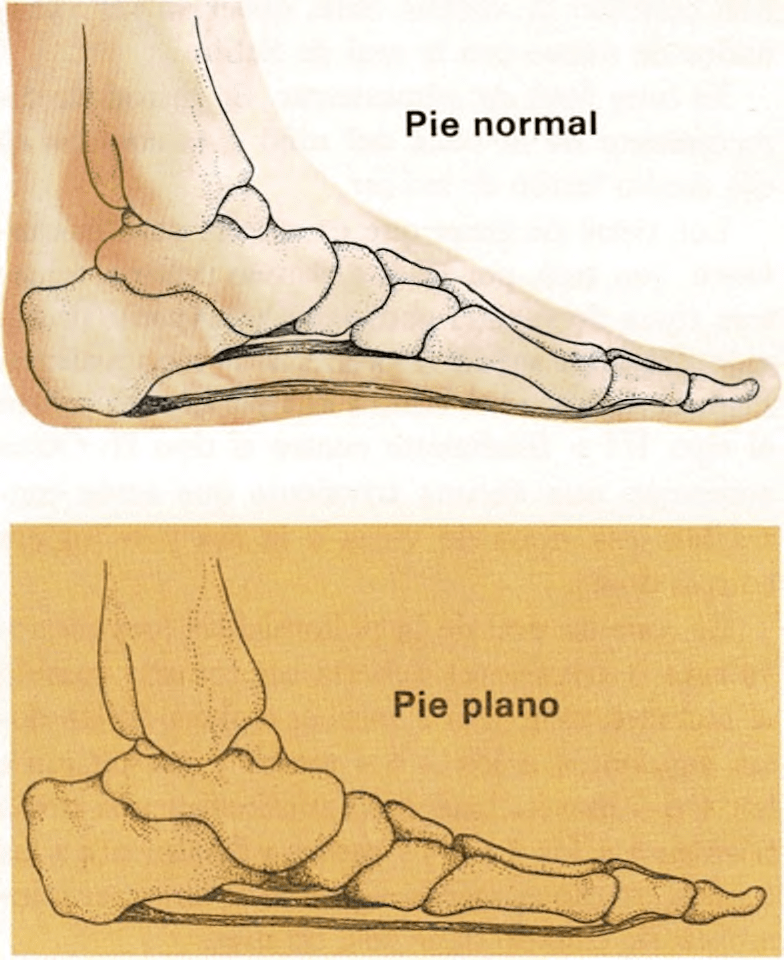

Pies planos

Cuando éstos son débiles, el arco o puente se aplana.

El arco del pie está formado por una serie de huesos, perfectamente relacionados entre sí, que constituyen una bóveda afirmada por músculos y ligamentos. Si estos músculos son débiles, el arco se relaja, se aplana y el niño tiene el pie plano, produciéndole molestias, dolor y cansancio fácil.

La mayoría de los niños pequeños parecen tener los pies planos, ya que sus pies son regordetes, con abundante grasa que enmascara el arco. A medida que el niño se ejercita en la marcha, los músculos se fortifican y sostienen los huesos del pie, formando un arco firme. Si a los dos años, todavía parece tener los pies planos, se queja de dolor en ellos o en las piernas o se cansa fácilmente, se consultará al médico, quien puede aconsejar unas plantillas especiales para los zapatos.

Hasta los dos años el niño debe llevar zapatos suaves, con una suela flexible, que permitan a los músculos de sus pies y tobillos, moverse y fortalecerse.